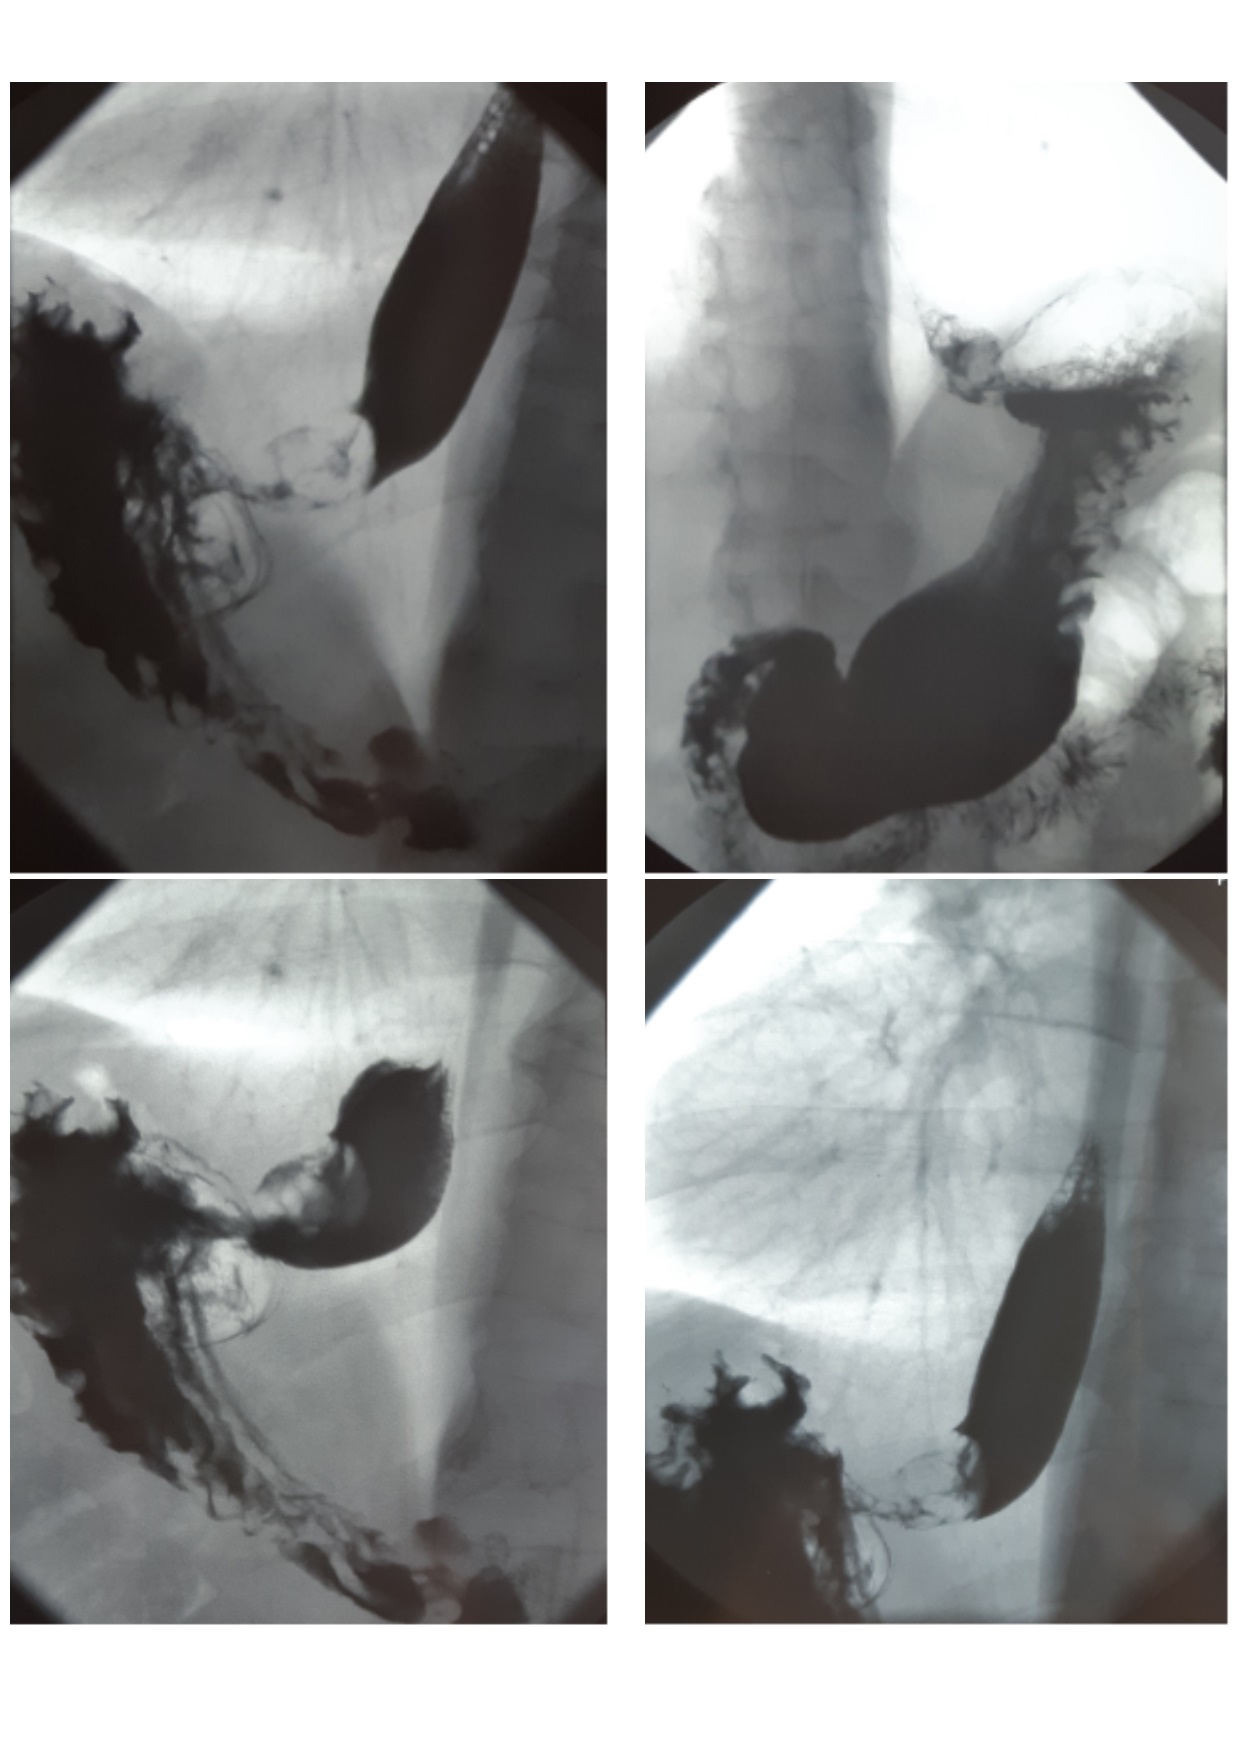

Contrast multiposition examination of the esophagus, stomach, duodenum after peroral intake of barium sulfate suspension (X-ray examination and X-ray photography in the frontal, lateral and oblique projections) revealed signs of cardioesophageal cancer (Figure 1).

Fig. 1. Radiographic contrast study of the esophagus and stomach: In the abdominal part of the esophagus and in the cardial part of the stomach a defect of filling is determined 4 x 3 cm with irregular edges, mucosal folds in the zone are not observed. Against the background gas bubble of the stomach the shadow of the tumorous formation is visualized. The fasting stomach contains insignificant amount of fluid and mucus. Emptying of the contrast substance from the stomach is not disturbed. The bulb and other parts of the duodenum are without changes